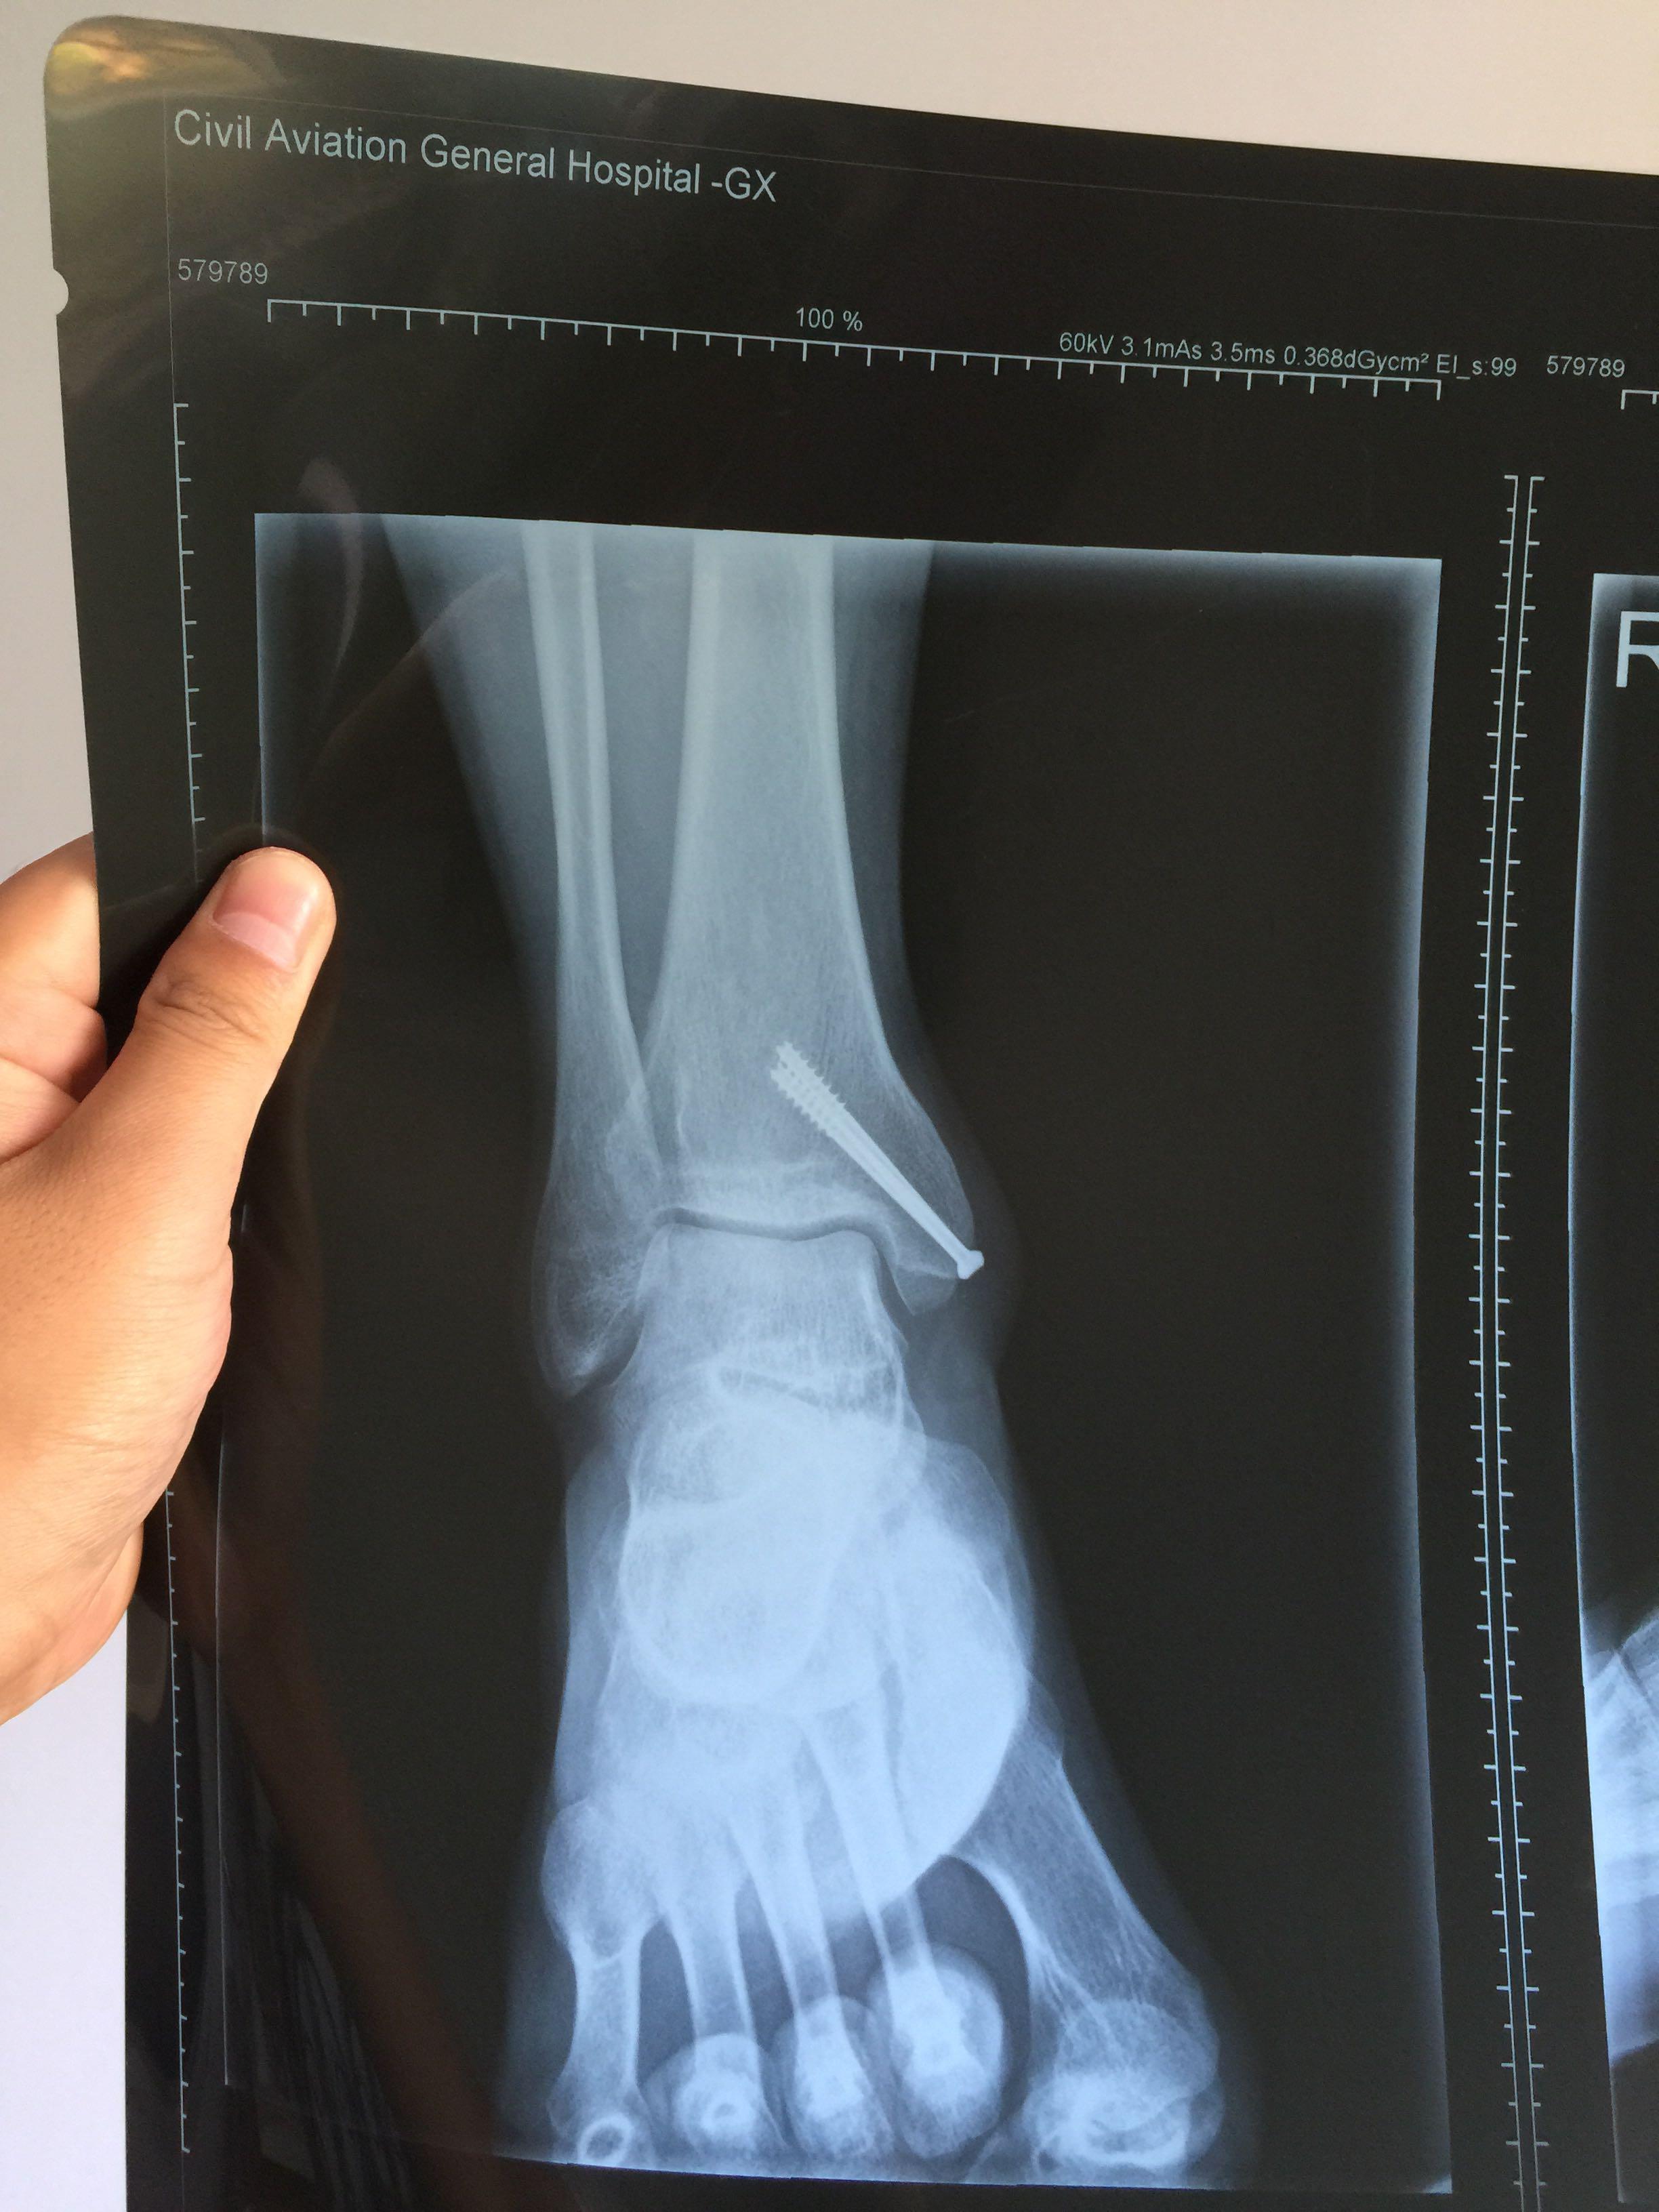

脚内踝骨折片子

脚内踝骨折 - 知乎